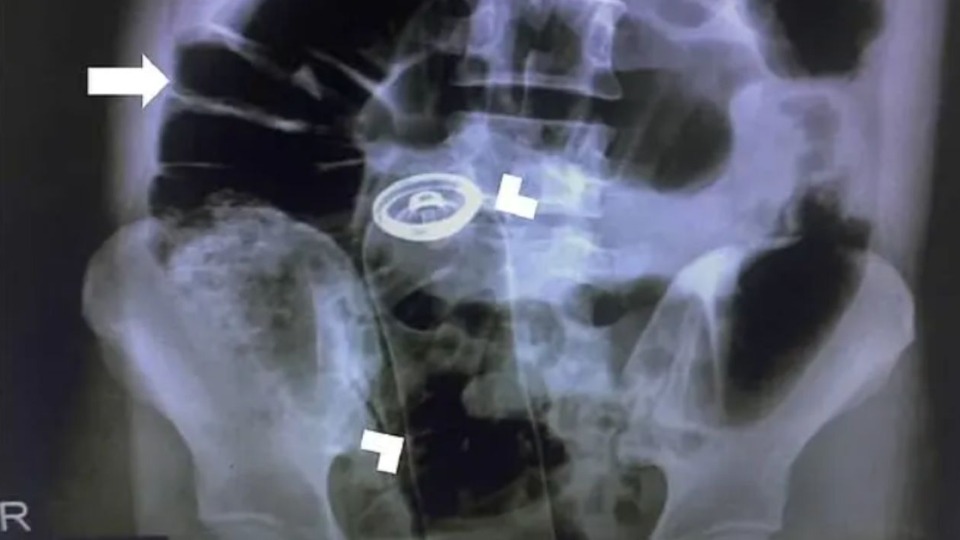

Um homem precisou de atendimento médico no Hospital João Paulo II, em Porto Velho (RO), ao introduzir um frasco de desodorante no reto. O caso ocorreu na última quarta-feira (12).

Conforme informações obtidas pelo Portal SGC, o homem chegou no Hospital João Paulo II e contou que estava sentindo dores fortes na barriga. Logo em seguida, ele contou que introduziu um frasco de desodorante no reto e não conseguiu tirar.

Então, a equipe realizou os procedimentos de praxe para fazer a remoção do objeto. Logo em seguida, o homem foi submetido a um procedimento cirúrgico para a retirada do frasco. O hospital não divulgou o estado de saúde do paciente.